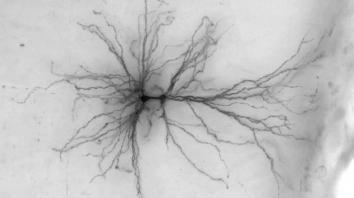

脑科学突破进展 计算机虚拟可活动人脑神经细胞模型

数世纪以来,科学家对大脑奥秘的了解仍然十分有限。艾伦脑科学研究所的科学家取得了突破性神经科学研究成果,通过大数据计算机创造出了活动的虚拟脑神经细胞模型,该研究能够使今后对人脑和器官的探究过程更加便利和深入。这项计算机模拟人脑神经细胞3D模型能够虚拟活体人脑细胞运作,其基于外科手术团...